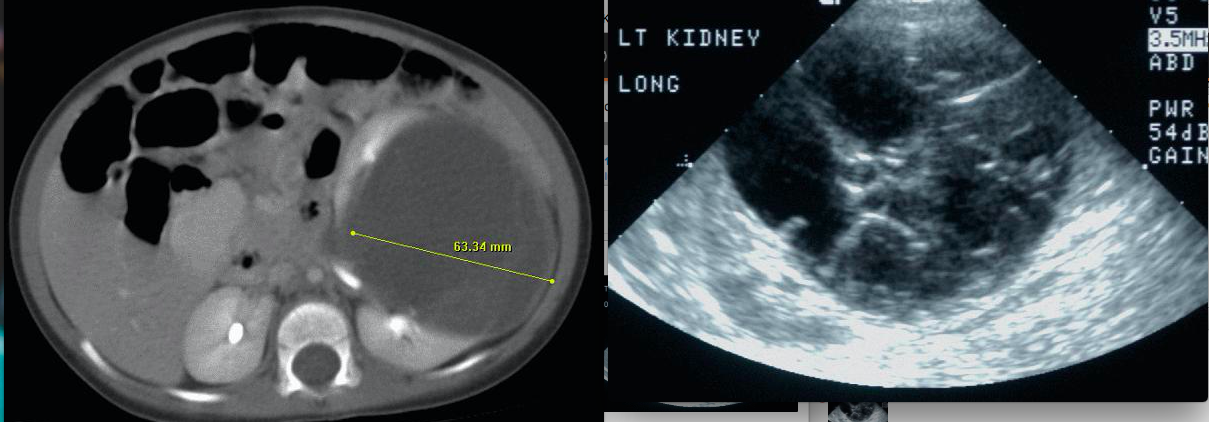

A three-year-old girl has a febrile UTI. Ultrasound and CT scan are shown. The next step is:

2

The imaging studies show a large complex cystic lesion that is not the result of an infectious process. The lesion is not typical for inherited cystic disease and parental evaluation is of no value. The differential diagnosis is either a cystic Wilms’ vs. a multilocular cystic nephroma. Diagnosis and treatment should be made based on the pathology following a nephrectomy.